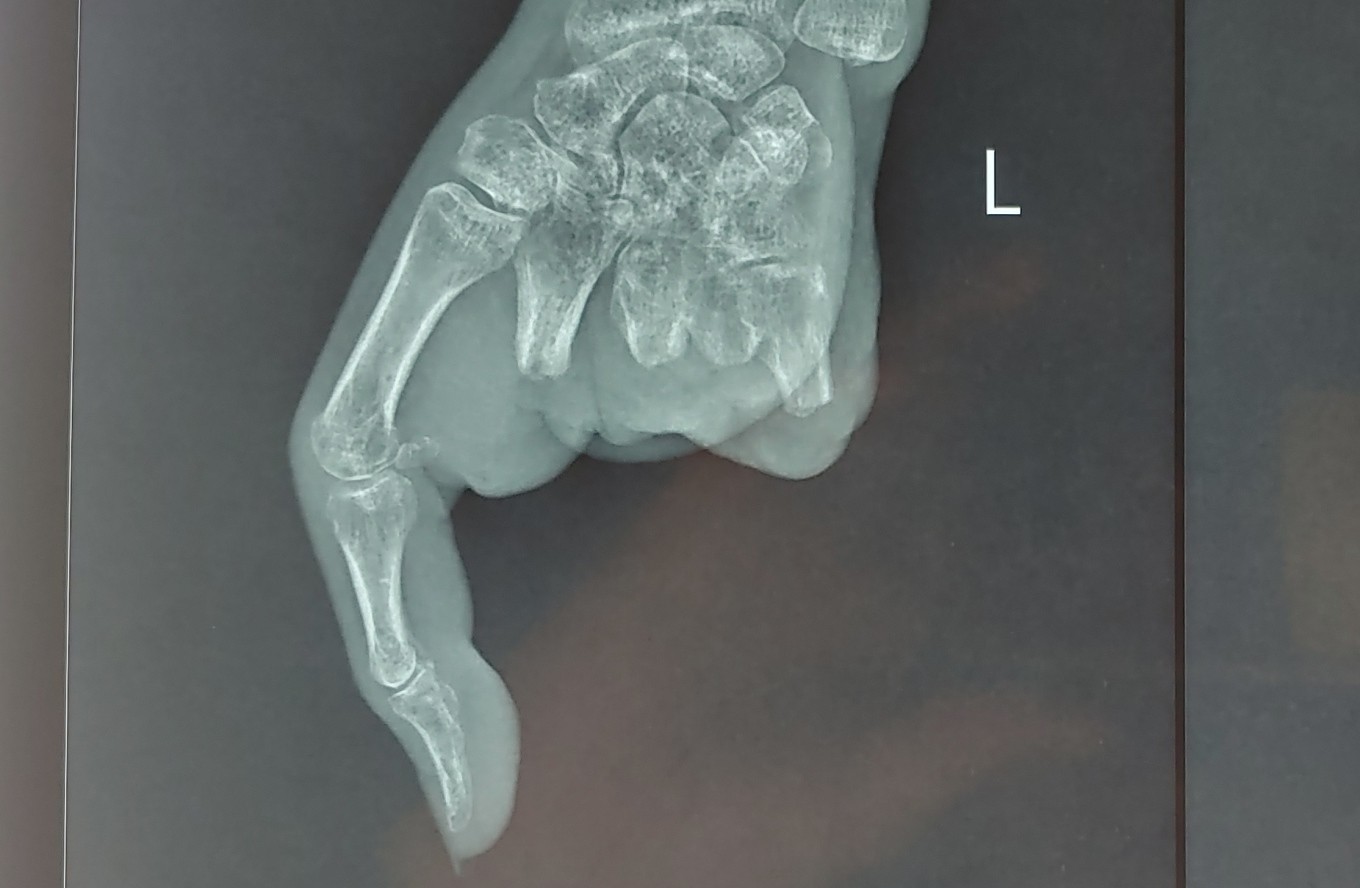

Sau phẫu thuật, hai ngón tay được nối của bệnh nhân phục hồi tốt, bác sĩ hướng dẫn tập luyện để phục hồi vận động ngón tay mới.

Đến nay, phần mỏm cụt tay bệnh nhân ổn định, không có dấu hiệu nhiễm trùng, bệnh lý nền được kiểm soát tốt, các bác sĩ tiến hành ca ghép hai ngón chân thành hai ngón tay.